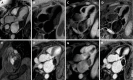

Cardiac masses diagnosis and treatment are a true challenge, although they are infrequently encountered in clinical practice. They encompass a broad set of lesions that include neoplastic (primary and secondary), non-neoplastic masses and pseudomasses. The clinical presentation of cardiac tumors is highly variable and depends on several factors such as size, location, relation with other structures and mobility. The presumptive diagnosis is made based on a preliminary non-invasive diagnostic work-up due to technical difficulties and risks associated with biopsy, which is still the diagnostic gold standard. The findings should always be interpreted in the clinical context to avoid misdiagnosis, particularly in specific conditions (e.g., infective endocarditis or thrombi). The modern multi-modality imaging techniques has a key role not only for the initial assessment and differential diagnosis but also for management and surveillance of the cardiac masses. Cardiovascular magnetic resonance (CMR) allows an optimal non-invasive localization of the lesion, providing multiplanar information on its relation to surrounding structures. Moreover, with the additional feature of tissue characterization, CMR can be highly effective to distinguish pseudomasses from masses, as well as benign from malignant lesions, with further differential diagnosis of the latter. Although histopathological assessment is important to make a definitive diagnosis, CMR plays a key role in the diagnosis of suspected cardiac masses with a great impact on patient management. This literature review aims to provide a comprehensive overview of cardiac masses, from clinical and imaging protocol to pathological findings.